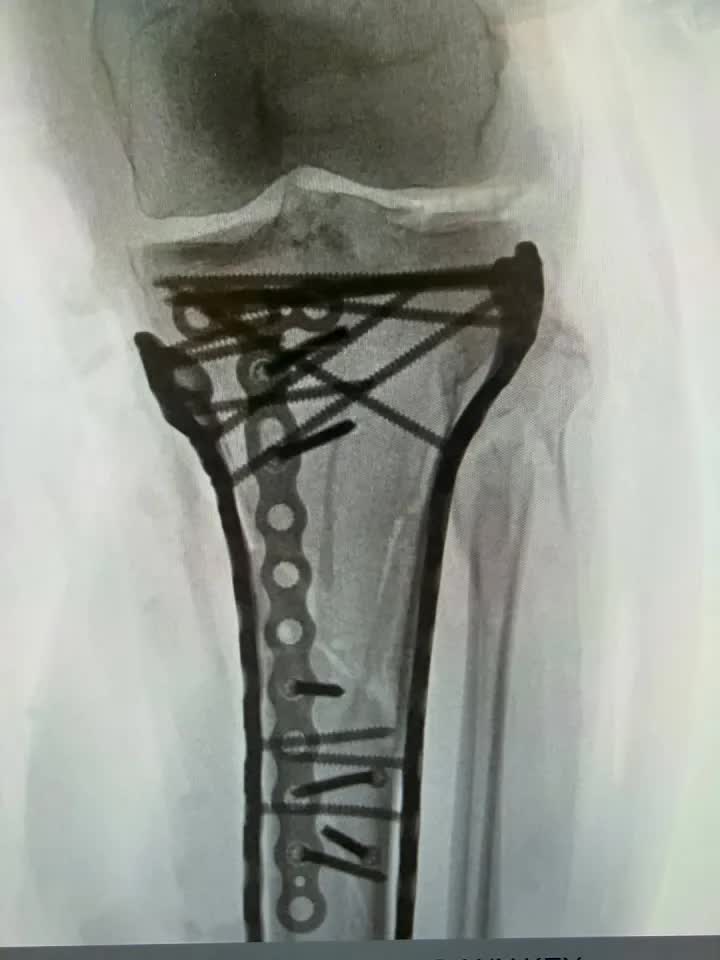

Ngay lập tức, một chiếc trực thăng cứu hộ đã đưa cô thẳng đến bệnh viện. Kết quả chụp chiếu khiến tất cả phải rùng mình: Xương chày bị gãy phức tạp, xương mác và mâm chày vỡ vụn. Nguy hiểm hơn, Lindsey mắc phải hội chứng chèn ép khoang - tình trạng máu tích tụ cực độ nghiền nát cơ bắp và dây thần kinh, buộc các bác sĩ phải đứng trước quyết định giữ hay bỏ đôi chân của cô.

Vonn đã trải qua một ca phẫu thuật lớn để điều trị vết gãy xương "phức tạp" (Nguồn ảnh: instagram @lindseyvonn)

Sau 2 tuần "chiến đấu" trong bệnh viện với những ca phẫu thuật kéo dài 6 tiếng đồng hồ, Lindsey Vonn vừa chính thức được xuất viện. Cô nghẹn ngào chia sẻ trên mạng xã hội: "Đây là điều khắc nghiệt và đau đớn nhất tôi từng đối mặt, nhân lên 100 lần. Bác sĩ Tom Hackett đã cứu mạng tôi, ông ấy đã thực hiện phẫu thuật mở cả hai bên chân để cơ bắp được 'thở', cứu tôi khỏi thảm cảnh phải cắt bỏ đôi chân của mình".